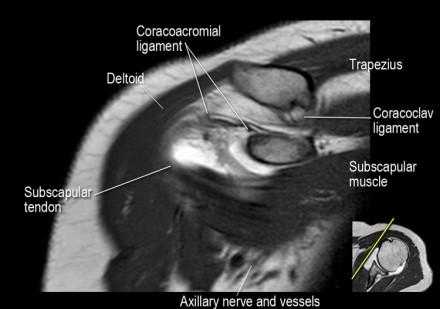

Нормальная корональная анатомия плечевого сустава и контрольный список

- обратите внимание на клювоакромиальную связку (coracoacromial ligament).